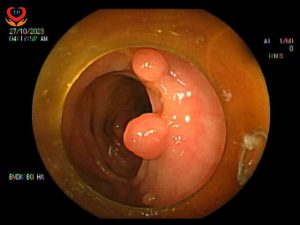

NỘI SOI ĐẠI TRÀNG PHÁT HIỆN HƠN 10 POLYP

Trong quá trình nội soi, bác sĩ đã phát hiện hơn 10 polyp nằm rải rác ở đại tràng, nguy hiểm hơn một số polyp đang có hiện tượng xung huyết gây ra đau đớn cho bệnh nhân.

Bác sĩ Đỗ Trọng Đức cùng các điều dưỡng, với kinh nghiệm cũng như sự hỗ trợ của hệ thống nội soi hiện đại, đã tiến hành cắt toàn bộ polyp ở vị trí đại tràng.